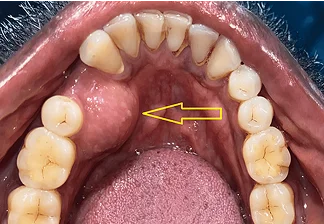

At Faith Hospital, we are dedicated to providing comprehensive, advanced, and compassionate cancer care under one roof. Dr. Zuber Vaja, specializes in Oral and Head & Neck Cancer Surgery, offering personalized treatment plans tailored to each patient’s unique needs. With expert care and modern technology, we focus on healing that restores both health and confidence.

Dr. Zuber Vaja

Head & Neck Cancer Surgeon